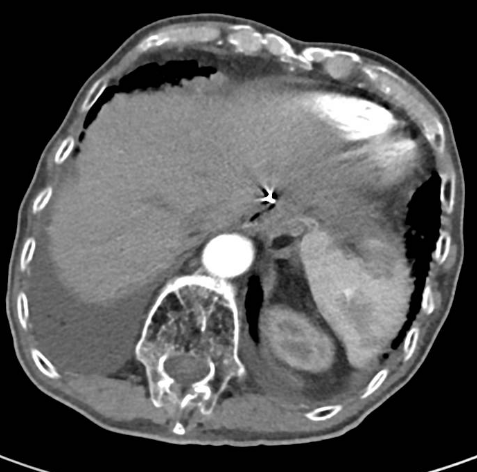

强化CT:1、符合胃部分切除术后,吻合口壁增厚伴食管下段扩张;2、胆囊结石:胆总管结合;3、肠淤张;4、前列腺增大;5、动脉硬化。

PET-CT检查:1、胃癌大部切除术后改变;肝左外叶近包膜下高代谢结节(于临近胃食管吻合口分界欠清),考虑肝转移。2、右肺中上叶多发结节伴代谢轻度增高;双肺间质纤维化;双肺泡性气肿;经根部气管憩室;贫血;动脉硬化;双侧胸膜增厚;右肺门及纵隔内多发淋巴结增生。

行CT引导下肺部肿物穿刺活检术,病理回报:(肺穿刺物)结合HE形态及IHC支持为腺癌,结合病史及IHC表型考虑转移可能性大,请结合临床。免疫组化结果:TTF-1(-),HER2(+++)

△ 2019.7影像学检查

2020-01-08复查腹部CT:与患者前片(2019-7-8)比较显示:食管胃吻合口区低密度病变范围较前缩小。所示腹部其余病变较前未见明显变化,双肺片状高密度影,双侧胸腔积液。

△2020.01腹部CT